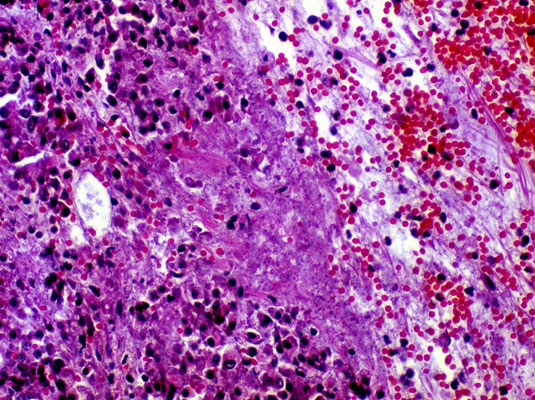

Acute hemorrhagic pancreatitis, H&E.

Acute hemorrhage with coagulation necrosis of acinar tissue.